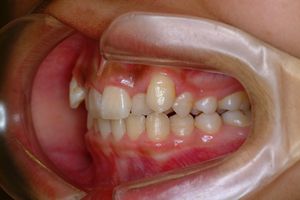

治療前 の 正面 です 動く矢印治療後 の 正面 です